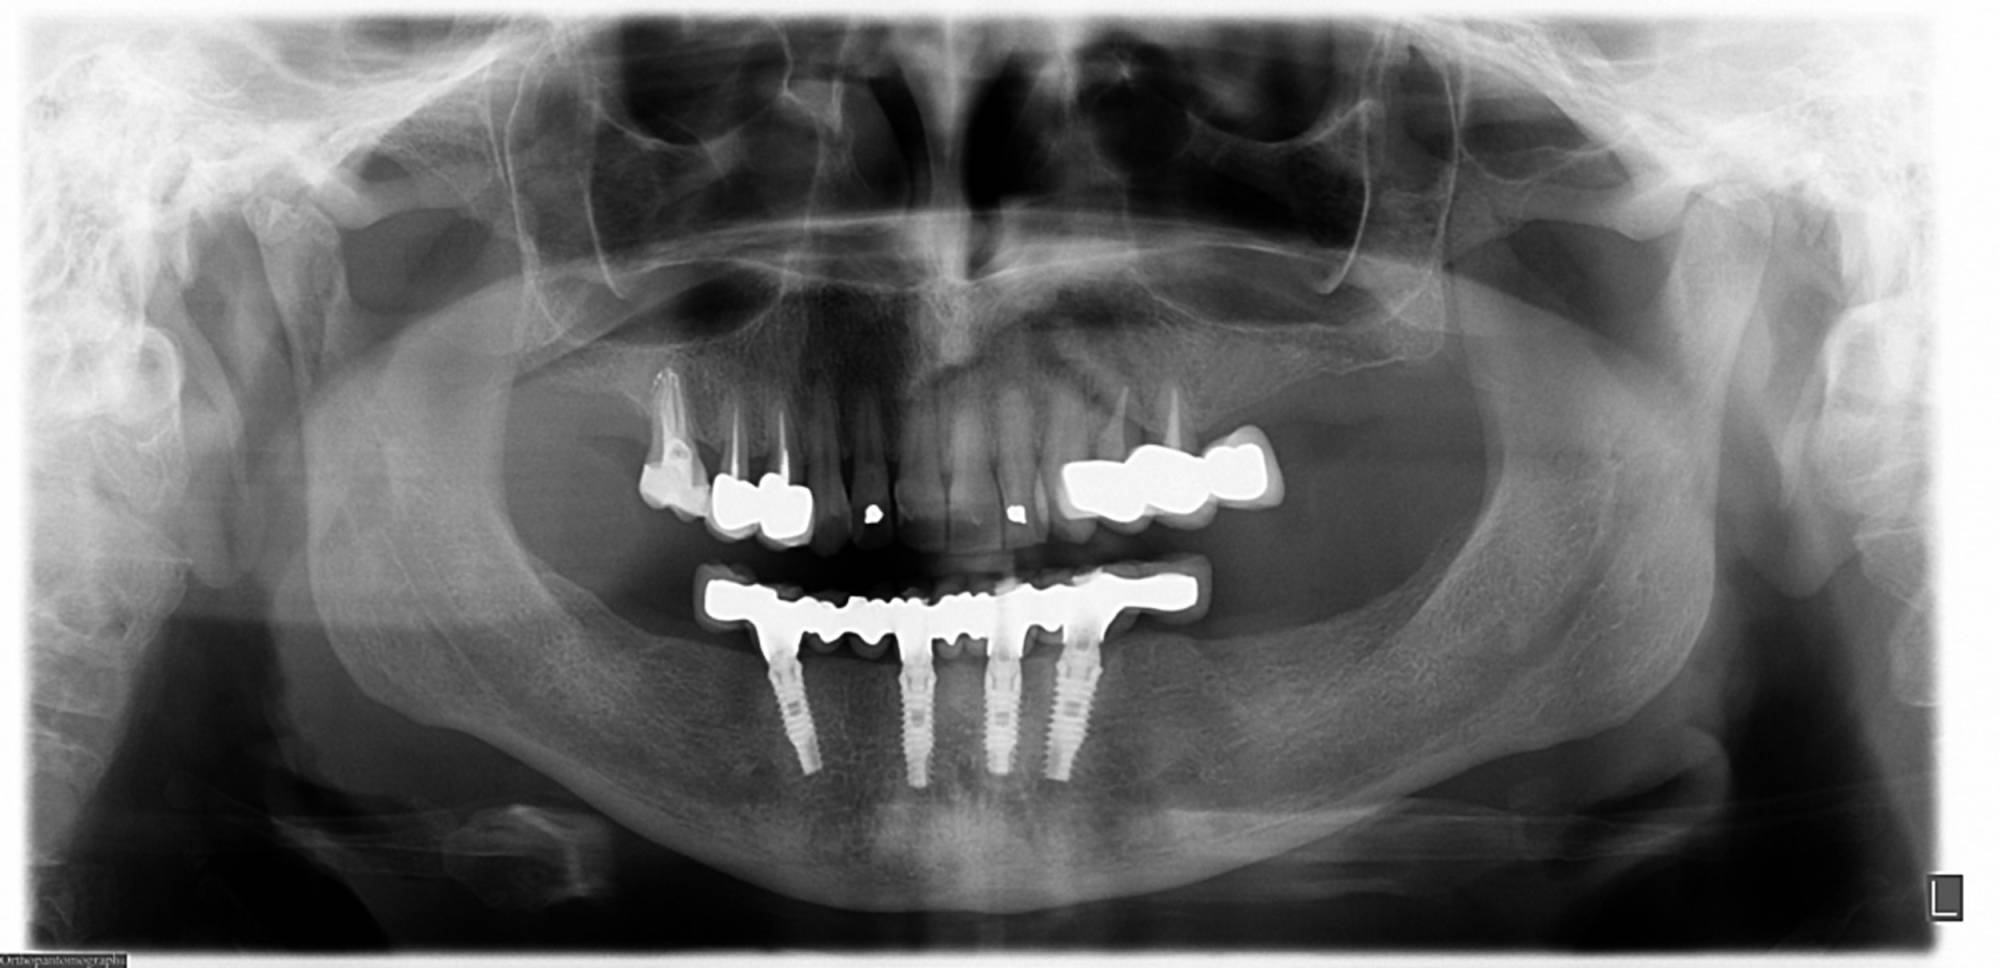

Una tecnica recente e molto apprezzata è l’implantologia computer guidata. L’anatomia della zona da operare è studiata con la Tomografia Computerizzata, simulando al computer, con un software di alta precisione 3D, il posizionamento degli impianti. Sulla base dei dati elaborati dal software si realizza in laboratorio una mascherina chirurgica che guiderà gli strumenti e gli impianti nella corretta posizione nell’osso del paziente, rendendo l’intervento più sicuro e veloce.